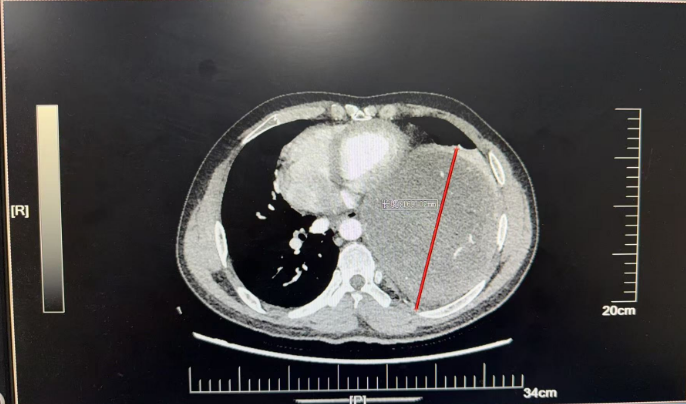

近日,北京天坛医院胸外科团队在多学科协作下,历经4小时,成功为患者完整切除左侧胸腔内直径近19厘米的巨大神经鞘瘤。此次手术的顺利完成,不仅彰显了北京天坛医院胸外科的精湛技术,更体现了多学科协作在疑难重症救治中的关键作用。

为寻求一线生机,杜先生通过熟人介绍并结合网上查询,慕名找到北京天坛医院胸外科主任医师杨增。医院胸CT检查结果令人揪心,成年人一侧胸腔宽度大约10-15厘米,而杜某的肿瘤直径近19厘米,占据了左侧多半个胸腔,把心脏和主动脉都挤偏了,原本竖直的主动脉已经弯到了右侧。再继续发展,一旦压迫到降主动脉,就会引发急性心衰,随时可能猝死。但更棘手的是,如果进行手术,该肿瘤为实性肿瘤,无任何囊变,血运极其丰富,且与左肺下叶致密粘连,甚至可能累及脊髓,手术中稍有不慎就可能导致心脏骤停、心律失常、大出血、截瘫等严重并发症。“不能因为风险高就放弃患者。”杨增了解情况后,当即决定将患者收入院。